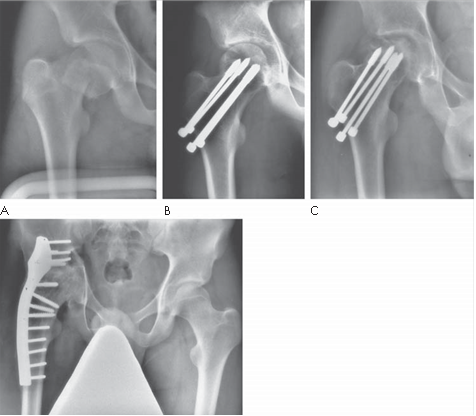

Reproduced from C. Bulstrode et al., Oxford Textbook of Trauma and Orthopaedics second edition, 2011, fi gure 7.16.1, p. 619, with permission from Oxford University Press.

What condition is illustrated here?

What is the aetiology and what risk factors are associated this condition? What other areas are commonly affected?

Can you describe any classification systems for this condition? What stage is shown in the radiographs above?

How would you manage a patient presenting with this condition? What treatment options are available?

Avascular necrosis of the femoral head with segmental collapse.

What is the aetiology and what risk factors are associated with this condition? What other areas are commonly aff ected?

Osteonecrosis (avascular necrosis/aseptic necrosis) occurs within the bone following loss of osseous blood supply. All cells within the area of aff ected bone die away; initially the organic and inorganic matrix are unaff ected. It commonly aff ects patients in the third, fourth, or fi fth decades of life. The aetiology of osteonecrosis is still not fully understood and is likely to be multifactorial. Factors thought to contribute to the disruption of the microcirculation include: z Trauma โ leading to macro- and microvascular interruption z Intravascular coagulation and thrombotic occlusion of microcirculation z Extravascular compression (โcompartment syndromeโ within bone) secondary to raised intraosseous pressures

Conditions associated with osteonecrosis include: z Trauma z Caisson disease (dysbaric osteonecrosis) z High alcohol intake z Systemic lupus erythematosus (SLE) z Corticosteroid usage z Ionizing radiation z Haemoglobinopathy (sickle cell anaemia) z Gaucherโs disease z Hypercoagulation disorders z Idiopathic (40 % )

Other areas most commonly aff ected are: medial femoral condyle; humeral head; talus; lunate (Kienbรถckโs disease); capitellum (Pannerโs disease); tarsal navicular (Kohlerโs disease); metatarsal head (Freibergโs disease).

Can you describe any classifi cation systems for this condition? What stage is shown in the radiographs above?

There are many classifi cation systems described for osteonecrosis of the hip. The Ficat and Arlet (1980) system describes X-ray appearances and is one of the most simple to use:

Stage 1: no bony changes seen on plain X-ray

Stage 2: sclerotic and cystic changes within the femoral head

Stage 3: subchondral collapse and distortion of the femoral head

Stage 4: secondary osteoarthritis with decreased joint space and articular collapse

T he radiographs show Ficat and Arlet stage 4 changes. There is distortion and collapse of the femoral head. The lateral view illustrates the โcrescent signโ associated with subchondral collapse.

How would you manage a patient presenting with this condition. What treatment options are available?

Treatment of early osteonecrosis of the femoral head aims to relieve pain and preserve the congruency of the hip joint. In the later stages of the disease arthroplasty procedures are usually required. Investigations used to help stage the disease include plain radiography, bone scans, and MRI.

Treatment for early stages (pre-collapse) may include: z Observation and analgesia z Treatment of any underlying medical conditions z Protected weight-bearing (little evidence)

z Core decompression ยฑ bone grafting or vascularized grafts Treatment for later stages (post-collapse) may include: z Realignment osteotomy z Arthrodesis z Replacement arthroplasty (conventional total hip arthroplasty or resurfacing)